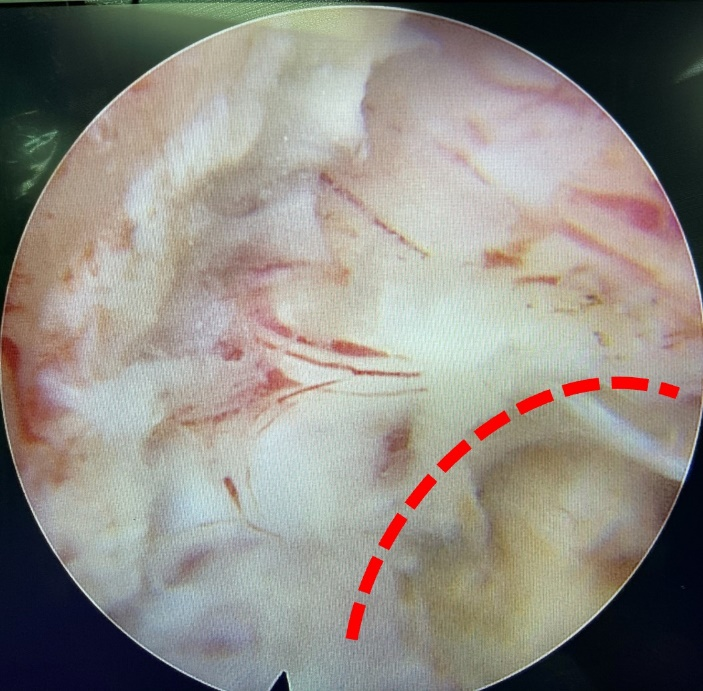

在充分准备下,我院骨科团队成功对该患者实施了内镜下Keyhole技术颈神经根管减压、颈椎间盘髓核摘除术。在椎板打磨出像钥匙孔一样的洞,扩大椎板间隙、侧隐窝及左侧神经根管,摘除突出髓核。 麻醉苏醒后,患者第一时间活动左上肢,发现已无疼痛感,他有力地握住医生的手,激动地向团队表达了感激之情:“我的手终于可以放下来了,谢谢你们帮我解决了大问题”。